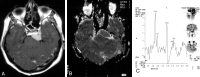

Background and purpose: MR spectroscopy and apparent diffusion coefficient (ADC) calculation have been used frequently for tumor grading and differentiation during the last decade. We evaluated whether the combination of these two techniques can improve the diagnostic effectiveness of MR imaging in patients with brain tumors.

Methods: Forty-nine patients with histologically proved brain tumors (eight high- and 12 low-grade astrocytomas, eight metastases, eight nonastrocytic gliomas, seven meningiomas, three dysembryoplastic neuroepithelial tumors (DNETs), and three tuberculomas) were prospectively evaluated with contrast material-enhanced MR imaging, single-voxel proton MR spectroscopy (TE = 135 ms), and diffusion-weighted imaging (b = 0, 500, and 1000 s/mm(2)) before surgery.

Results: MR spectroscopy could differentiate benign from malignant tumors but was not useful in grading malignant tumors. In the differentiation of malignant from benign tumors, N-acetylaspartate (NAA)/choline (Cho), NAA/Cho + creatine (Cr), lactate/Cr, and alanin/Cr ratios (P <.001) were statistically more significant than NAA/Cr and lactate/lipid ratios (P <.05). Increase in lipid/Cr and alanin/Cr ratios could distinguish metastasis and meningiomas from other tumors, respectively (P <.001). DNETs could be diagnosed by their normal spectra and high ADC values (116.25 +/- 6.93 x 10(-3) mm(2)/s). Increase in lactate/Cr ratio correlated with degree of malignancy (r = -0.71). ADCs were effective for grading malignant tumors (P <.001) but not for distinguishing different tumor types with the same grade. High-grade malignant tumors (87.16 +/- 10.41 x 10(-3) mm(2)/s) had significantly lower ADC values than did low-grade malignant (115.33 +/- 11.67 x 10(-3) mm(2)/s) and benign (107.69 +/- 8.05 x 10(-3) mm(2)/s) tumors. Peritumoral ADCs were significantly higher in low-grade than in high-grade astrocytomas (P <.05).

Conclusion: Combination of calculated ADC values from tumoral core and specific relative metabolite ratios acquired by MR spectroscopy added more information to MR imaging in the differentiation and grading of brain tumors and were more useful together than each alone.